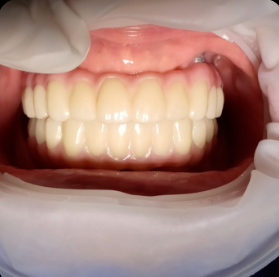

틀니가 잘 빠지고 불편해서 고민이세요?

예전으로 돌아가고 싶으신가요?

갈비도 뜯고.. 입가에 주름도 없고 팽팽하던 그때로...

많은 분들의 걱정,

디지털 풀아치가 해결해 드립니다